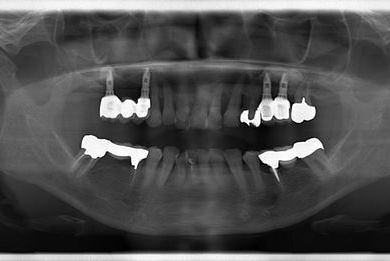

インプラントの症例写真 IMPLANT

骨再生インプラント治療

| 性別/年齢 | 女性 / 51歳 | ||||||||||||||||||||||||||||||||

| 治療方針 | サイナスリフトにより上顎洞を拳上し、インプラント治療を可能にする。 | ||||||||||||||||||||||||||||||||

| 治療内容 | インプラント3本(サイナスリフト)、ハイブリッドセラミッククラウン5本 | ||||||||||||||||||||||||||||||||